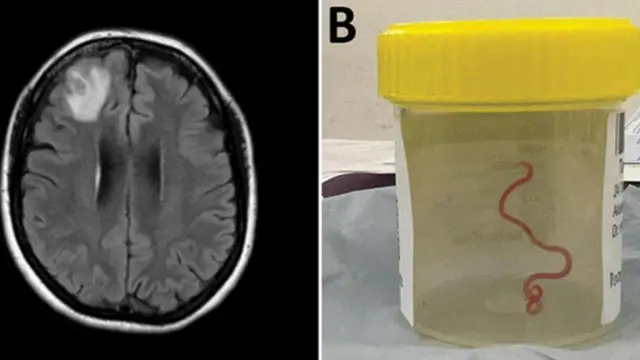

እቲ "ገመድ ዝመስል ኣቃውማ" ዘለዎ ሓሰኻ ካብቲ ዝሓለፈ ዓመት ኣብ ካንበራ ኣብ ሓንቲ ተሓካሚት ዝተገብረ መጥባሕቲ ቲሹ ዝወጽአ እዩ።

“[እቲ መጥባሕቲ ዝገብር ሓኪም] ገለ ወረጦ ወሲዱ ዘይንቡር ነገር ምስ ኣልዓለ፡ እቲ ዘይንቡር ድማ ፈለኽለኽ ዝብል ህያው 8 ሴንቲ ሜተር ዝዕቀን ፍኹስ ዝበለ ቀይሕ ሓሰኻ ምዃኑ ምስ ተረጋገጸ ኩሉ ሰብ ሰንቢዱ” ክብል ኣብ ኣብ ሆስፒታል ካንበራ ክኢላ ተላገብቲ ሕማማት ዝዀነ ሳንጃያ ሰናናያከ ገሊጹ።

ድሒሩ ኣብ ዝተገብረ መርመራ “ኣብ ውሽጢ የማናይ ቅድመ-ገጽ ሓንጎላ ዘይተለምደ ቁስሊ" ከም ዘሎ ተረጋጊጹ።

ናይዚ ጠንቂ ኣብ ወርሒ ሰነ 2022 ድሕሪ ዝተኻየደ መጥባሕተ’ዩ ተፈሊጡ።

ምንጪ ስእሊ, ANU